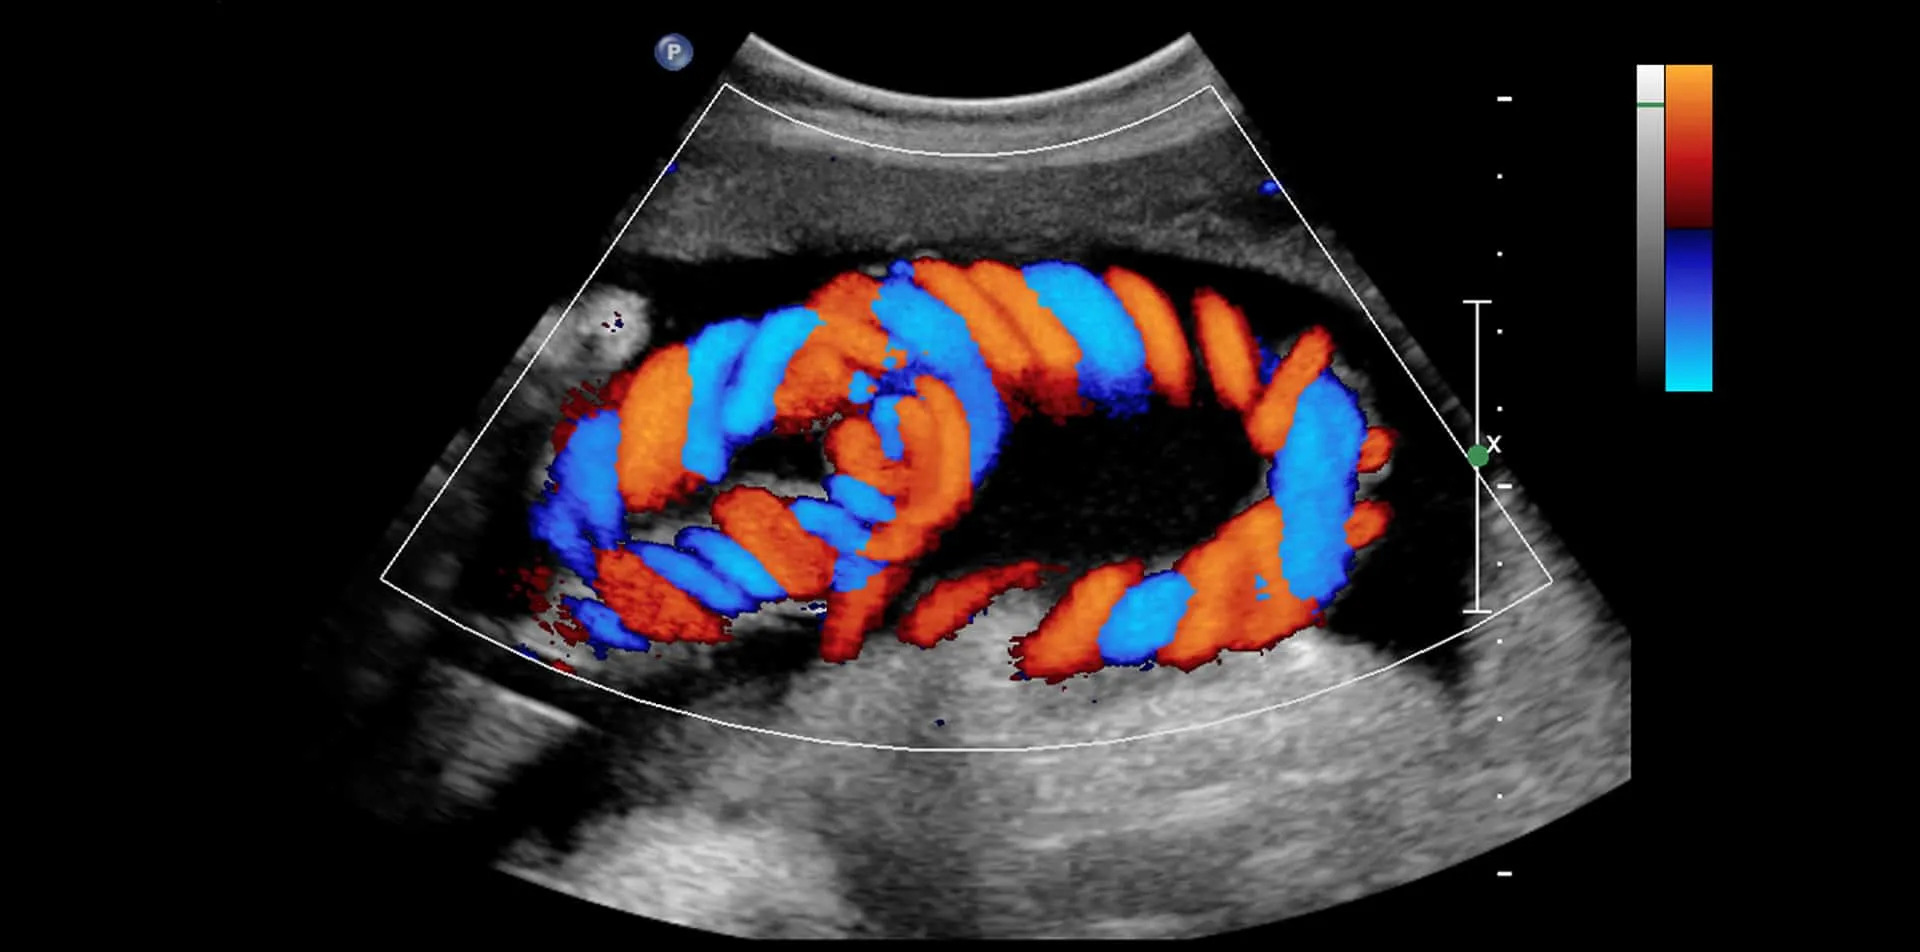

Color Doppler: Advanced Ultrasound Test for Blood Flow Evaluation

Color Doppler is a specialized ultrasound technique that visualizes and evaluates blood flow in arteries and veins. It helps diagnose vascular conditions such as deep vein thrombosis (DVT), varicose veins, peripheral artery disease (PAD), and other circulation problems. This non-invasive test provides real-time imaging, allowing early detection of blockages, narrowing, and abnormal blood flow patterns.

Color Doppler uses sound waves to create dynamic color images of blood flow inside blood vessels. It shows the speed and direction of blood flow, helping detect circulatory issues that may not be visible on routine ultrasound.

• The machine converts sound waves into color-coded blood flow images.

What Color Doppler Results Show

• Normal blood flow

• Slow or restricted flow (possible blockage)

• Reverse flow (venous valve leak)

• Complete obstruction (clot or severe narrowing)